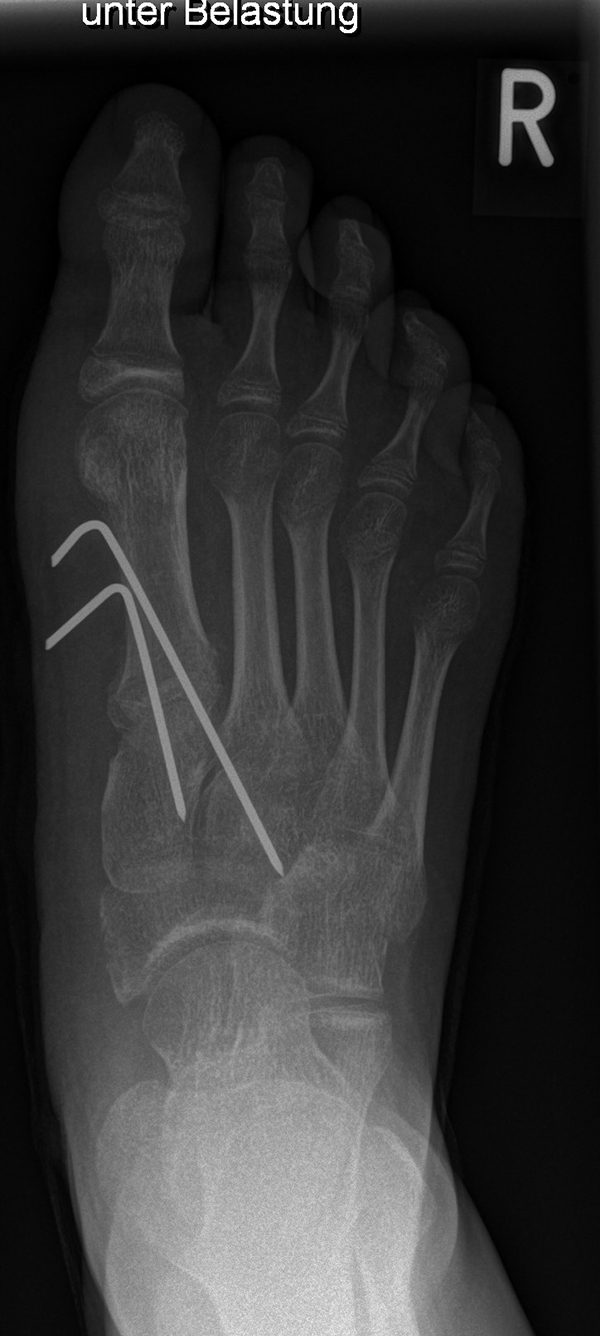

In der Regel bestehen aktive Wachstumsfugen bei Mädchen bis zum 12. und bei Jungen bis zum 14. Lebensjahr, mit Abweichungen von einem Jahr nach unten und nach oben. Präzise Informationen unter anderem darüber gibt das präoperative Röntgenbild (Abb. 2).

Abb. 2 a-c: offene Wachstumsfugen MT I Basis und Zehen (a), teilweise geöffnete Wachstumsfugen (b) und geschlossene Wachstumsfugen (c).

Zum Lesen der Bildbeschreibung und zur Vollansicht bitte die Bilder anklicken. Bilder: A. Helmers.